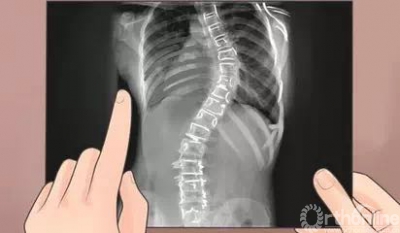

我国每年脊柱侧凸新发病人数以百万计,不仅影响身体发育,还给青少年造成心理阴影。关于脊柱侧凸的治疗,早发现、早治疗是关键,轻度的可以保守,但病情较重的、进展性的要尽早手术,且要根据患者个体差异制定个体化的治疗方案。

有针对性的功能锻炼是脊柱侧弯治疗的重要部分,但目前国内还没有系统锻炼方案,西京医院骨科罗卓荆主任带领团队立足上千例脊柱侧弯的诊治经验,结合国际最先进的体疗理念,开发出西京脊柱侧弯体疗教程(XiJing-Scoliosis Specific Exercise Program,XJ-SSEP),通过对躯干柔韧性、平衡性及侧弯局部进行针对锻炼,延缓脊柱侧弯进展,改善身体素质,强化心肺功能,更好的维持躯干的平衡及稳定性,提高孩子的生活质量。